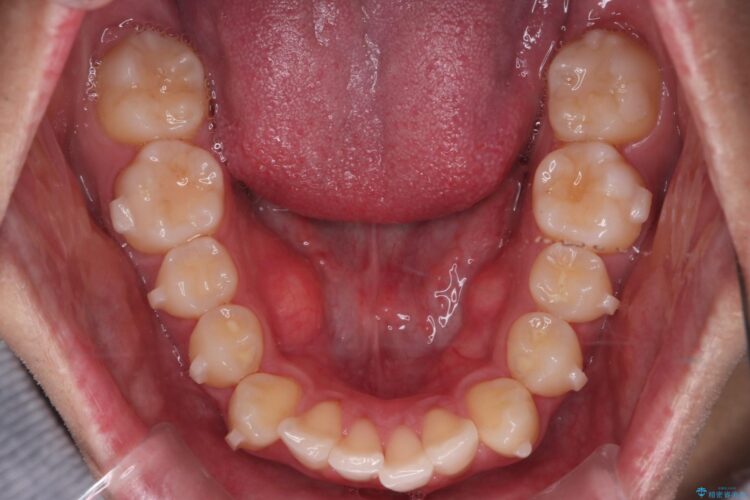

上の前歯が出ているのが気になるとご来院された患者様です。

IPR(歯と歯の間を削る処置)を行うことで、前歯の位置とがたつき整える治療計画を立てました。